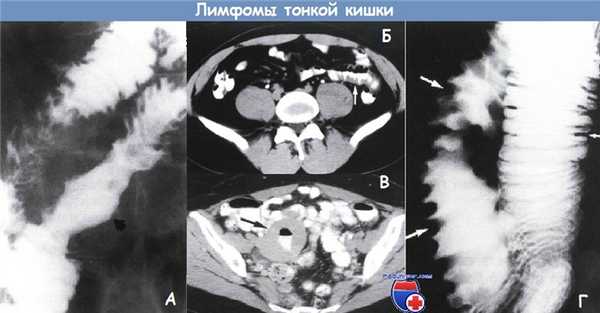

Лимфома тонкой кишки у мужчины 70 лет.

(а) При КТ с контрастированием визуализируется циркулярная инфильтрирующая опухоль (стрелки) тонкой кишки с аневризматическим расширением вовлеченного просвета.

(б) При ПЭТ-КТ с использованием 18F-FDG выявляется гиперметаболизм лимфомы тонкой кишки (стрелки). Множественные лимфомы тонкой кишки у мужчины 34 лет.

При КТ в коронарной проекции визуализируется циркулярное утолщение стенки (белые стрелки) в области терминального отдела подвздошной кишки с легким, гомогенным накоплением контрастного вещества.

Отмечается аневризматическое расширение вовлеченного сегмента. Выявляются множественные увеличенные лимфатические узлы (белые указатели) брыжейки.

Спаянные лимфатические узлы пережимают лимфатический сосуд (черные указатели) с образованием «симптома сэндвича».

Также сегментарное утолщение стенки отмечается в тощей кишке (черная стрелка). Визуализируется кишечно-кишечная инвагинация.

Было установлено, что опухоли тощей кишки и терминального отдела подвздошной кишки представляют собой лимфому Беркитта. Лимфома тонкой кишки (диффузная крупноклеточная В-клеточная лимфома) у мужчины 66 лет.

(а) На прицельной рентгенограмме при пассаже бария по тонкой кишке выявляется неравномерное утолщение складок кишки (стрелки).

(б) При КТ с контрастированием в коронарной проекции визуализируется сегментарное циркулярное утолщение стенки (стрелки) вовлеченного сегмента тонкой кишки с гомогенным накоплением контрастного вещества.